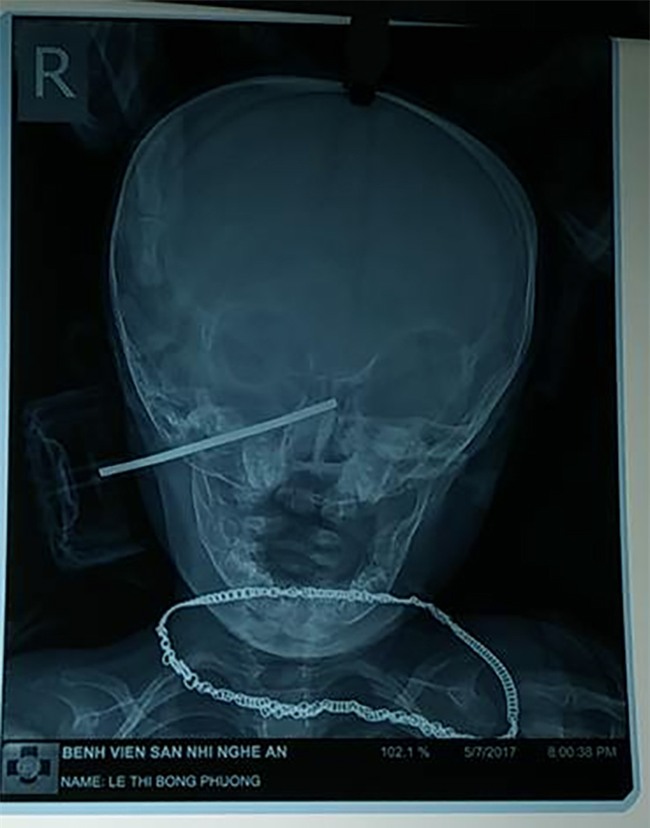

Sau đó các bác sĩ đã tiến hành đưa bệnh nhân đi chụp CT scanes sọ não để xác định được vị trí, đường đi và các tổn thương do dị vật này gây ra.

Hình ảnh chụp CT cho thấy dị vật găm sâu vào đầu bệnh nhân, đường đi phức tạp và nguy hiểm. |